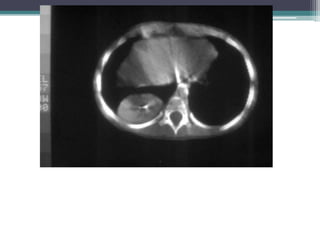

Two coronal T1 weighted images and one axial T2 weighted image from an MRI

exam from the 5th hospital day demonstrate a posterior mediastinal mass that

extends into the retrocrural regions of the chest bilaterally and that enhances

uniformly. There is no evidence of metastatic disease.

Dx-Sequestration, Extralobar

PA and lateralchest films from the day of admission demonstrate a large round opacity in the left lower lobe that abuts the diaphragm

Two coronal T1weighted images and one axial T2 weighted image from an MRI exam from the 5th hospital day demonstrate a posterior mediastinal mass that extends into the retrocrural regions of the chest bilaterally and that enhances uniformly. There is no evidence of metastatic disease. Dx-Sequestration, Extralobar